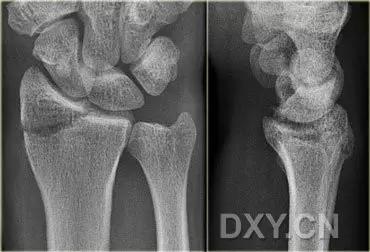

手腕部骨折

1. Barton 骨折

桡骨远端有移位的、不稳定的且经关节的桡骨远端骨折。可向掌侧也可向背侧移位。

(来源:radiology assistant)

2. Colles 骨折

桡骨远端骨折,伴有桡骨远端向背侧的移位,可以有或没有尺骨干的骨折。具有这几个特征:背侧粉碎、向背侧成角、向背侧移位且挠骨短缩的关节外骨折。

典型 colles 骨折,枪刺样、餐叉样畸形

3. Smith 骨折

桡骨远端骨折伴骨折远端向掌侧移位,也称为反 Colles 骨折。

来源:radiology assistant